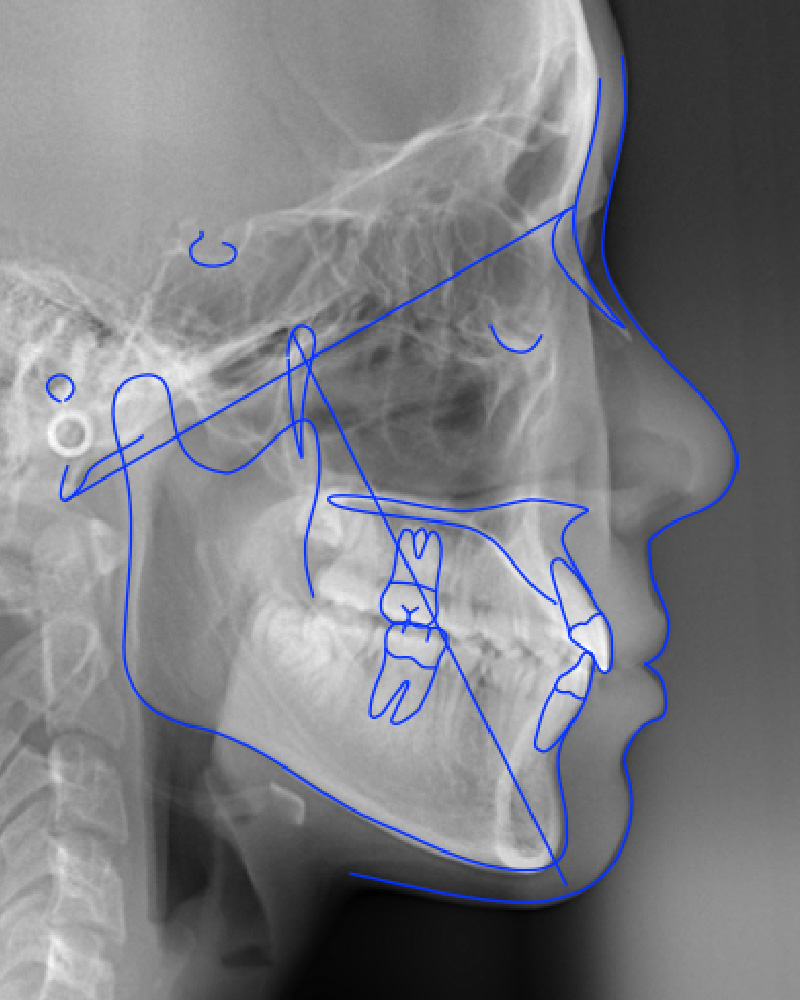

頭部X線規格写真

一時スプリントを装着して下顎は後退しましたが、その後下顎は反時計回りに大きく成長しているのがわかります。顎位を安定させるプロセス(スプリント治療)が、その後いかに大きな下顎の成長をもたらしたかを示しています。